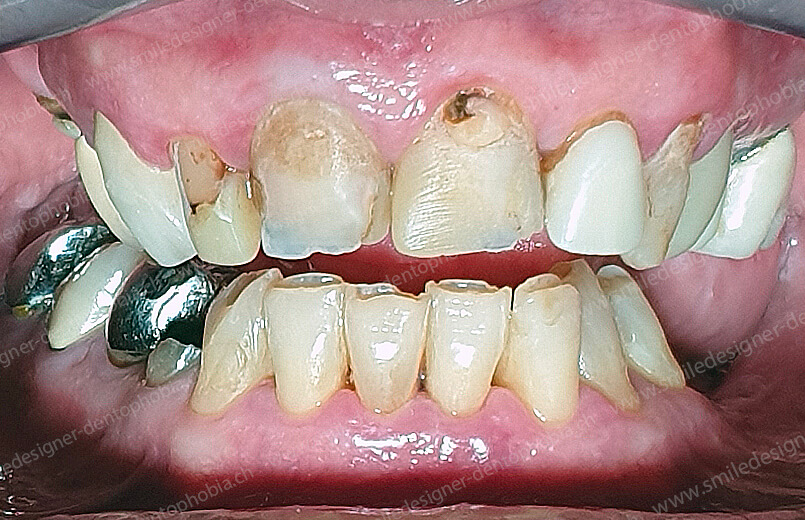

Cas clinique « GOLD STANDARD MCI » maxillaire : Bridge implanto-porté sans extension (ALL ON 8). Version définitive des bridges avec un cosmétique en céramique.

BRIDGE RÉSILIENT DE PREMIÈRE INTENTION DE MISE EN CHARGE IMMÉDIATE POUR UNE RESOCIALISATION IMMÉDIATE DE LA PATIENTE

CAS EN COURS D’OSTEOINTÉGRATION DES IMPLANTS.